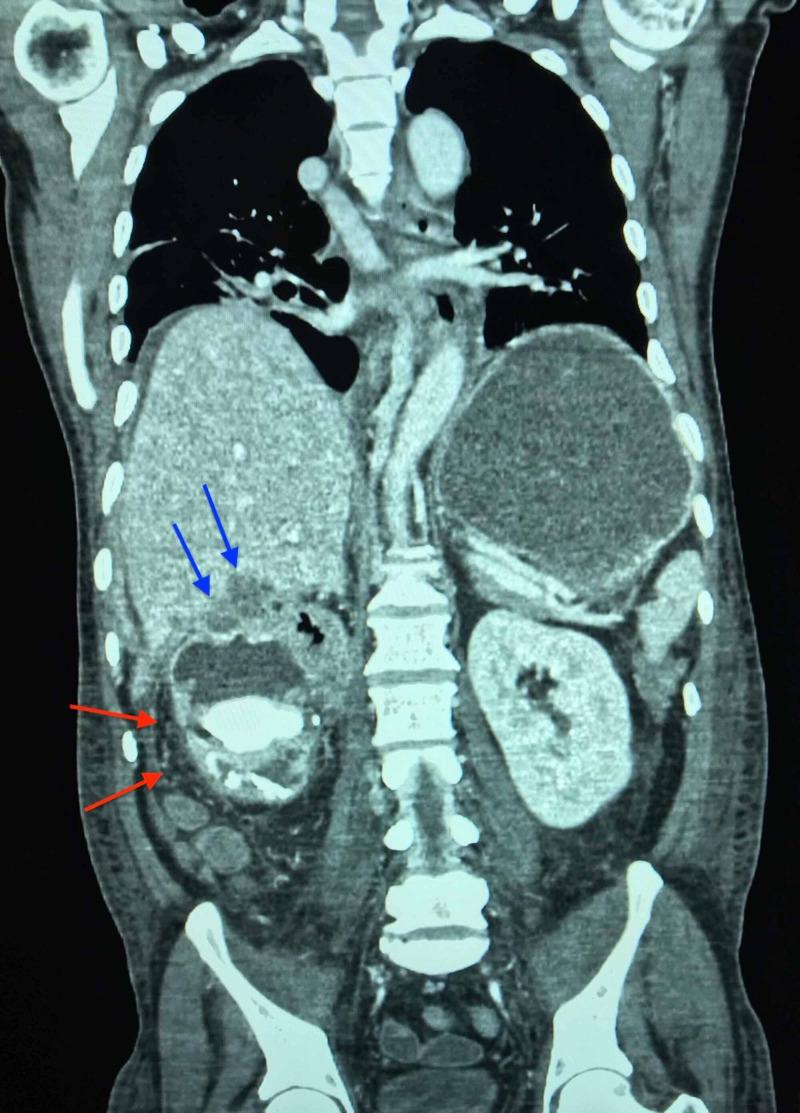

一例极为罕见的原发性肾鳞状细胞癌,其在放射影像学上表现为黄色肉芽肿性肾盂肾炎。

A Very Rare Case of Primary Renal Squamous Cell Carcinoma Presenting With Xanthogranulomatous Pyelonephritis on Radiological Imaging.

Xanthogranulomatous pyelonephritis (XGP) and primary renal squamous cell carcinoma (SCC) are both rare conditions that can present very similarly in a patient with renal staghorn calculi. We report a case of a 54-year-old male who presented with fatigue, vomiting and significant acute weight loss. The patient was initially believed to have XGP, but was ultimately diagnosed with both XGP and primary renal SCC. This case report and literature review is meant to elucidate the similarities and differences between XGP and primary renal SCC as both can be diagnostically challenging.

摘要

黄色肉芽肿性肾盂肾炎(XGP)和原发性肾鳞状细胞癌(SCC)都是罕见疾病,在患有肾鹿角形结石的患者中表现可能非常相似。我们报告一例54岁男性病例,该患者出现疲劳、呕吐和明显的急性体重减轻。患者最初被认为患有XGP,但最终被诊断为同时患有XGP和原发性肾SCC。本病例报告和文献综述旨在阐明XGP和原发性肾SCC之间的异同,因为两者在诊断上都具有挑战性。